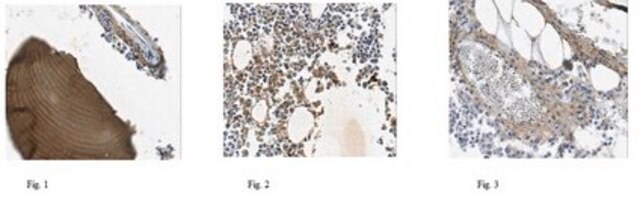

Evaluated by Immunohistochemistry Analysis in human bone tissues.

Immunohistochemistry Analysis: A 1:50 dilution of this antibody detected COL1A2 in human bone tissues.